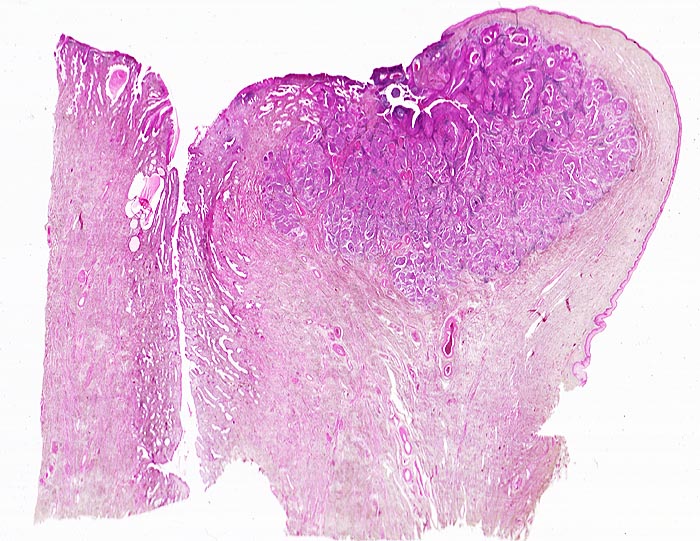

Invasives Plattenepithelkarzinom der Zervix

Scharf begrenzter, von der vorderen Muttermundslippe im Bereich der Umwandlungszone ausgehender Tumor. Zervikalkanal.

Die Umwandlungszone liegt dort, wo das metaplastische Plattenepithel der Ektozervix die endozervikalen Drüsen überwächst. An dieser Stelle finden sich am häufisten präneoplastische und neoplastische Veränderungen des Zervixepithels.

Histologie

Scan